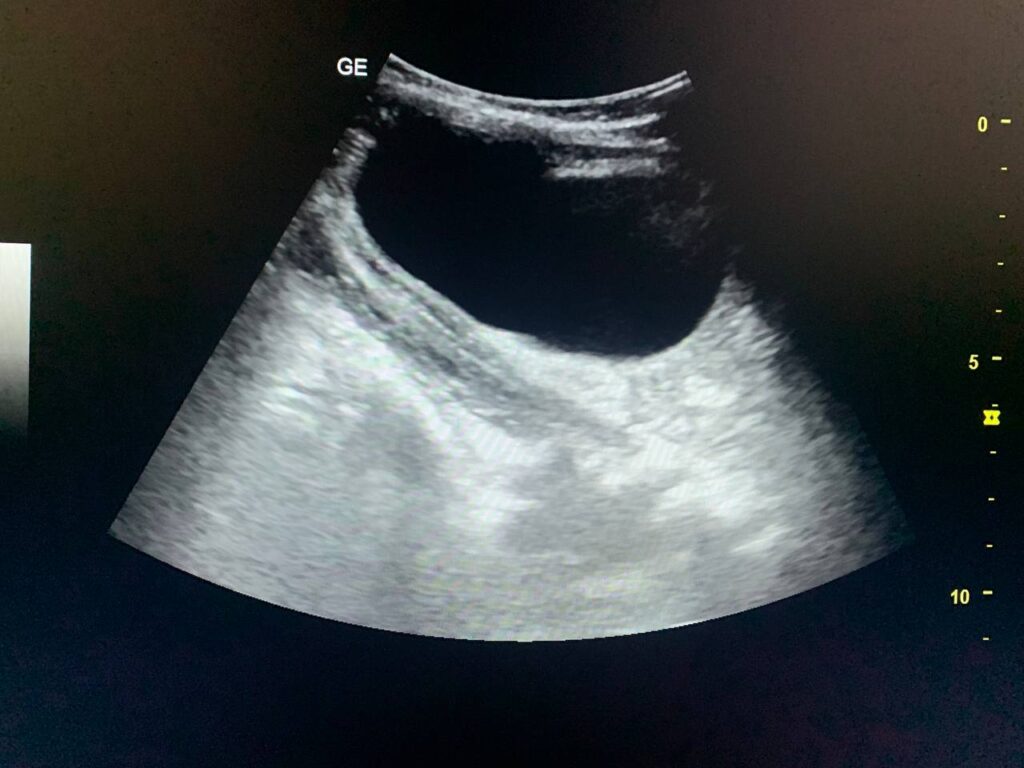

presence of circumscribed avascular cystic mass 58x47mm in the right subhepatic region ,adjacent to the right lobe segment 7 , other circumscribed avascular cystic mass 77x38mm seen in the left para cholic region , could amebic cyst ? , congenital ? others ? please for further study